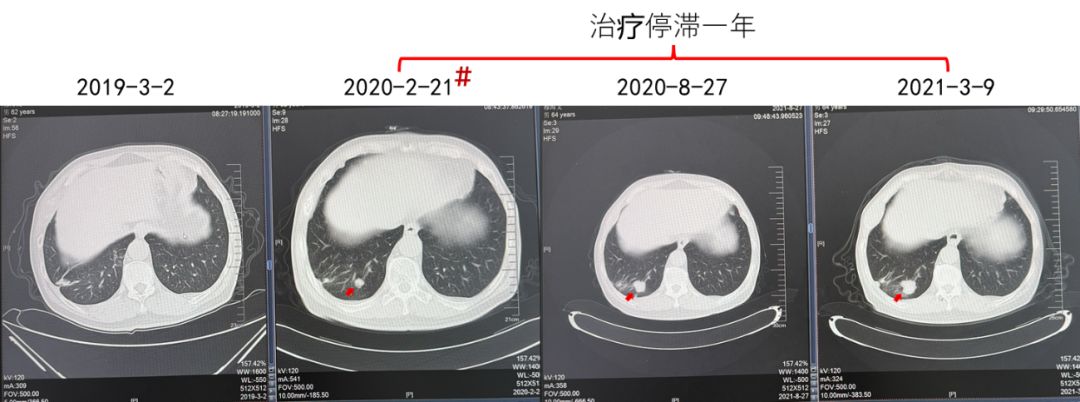

(治疗停滞1年,患者对侧肾上腺肿瘤发生进展)

由于患者中间治疗停滞一年,可能导致了肿瘤的进一步发展,因而需要针对对侧肾上腺肿瘤进行治疗。对于一线TKI单药治疗后进展的患者,目前多推荐更改为以ICI为基础的靶免联合治疗方案。而对于靶免联合治疗后进展的患者,需要充分考虑患者危险因素与危险分层、药物疗效与耐受性,综合选择治疗方案。